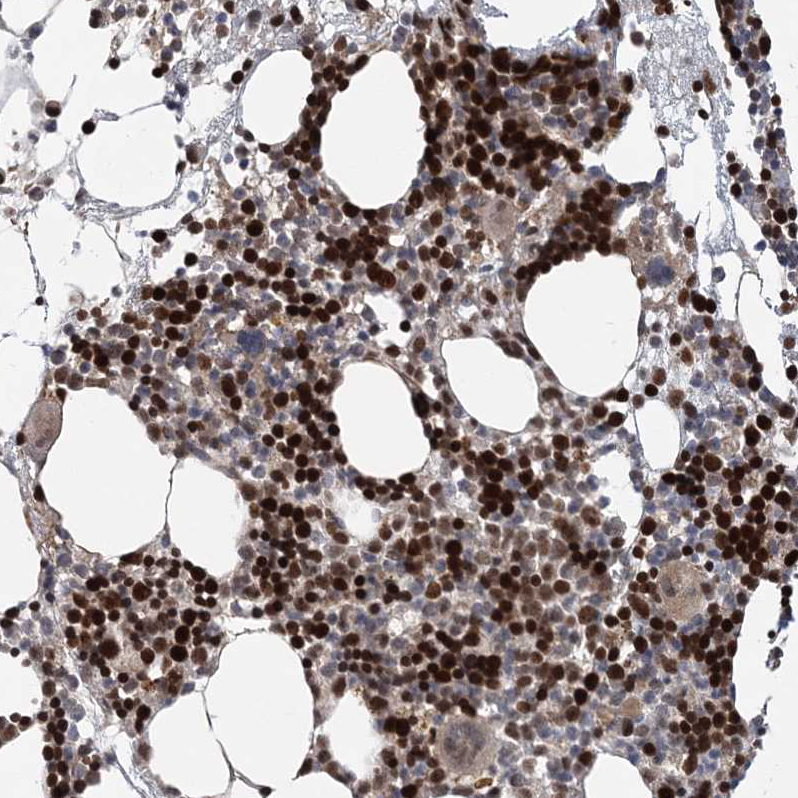

Immunohistochemical staining of human bone marrow shows strong nuclear positivity in hematopoietic cells.